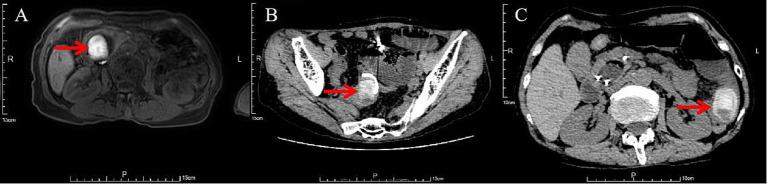

Gallstone ileus is a rare but severe complication of gallstone disease and is typically caused by the formation of a fistula between the biliary and gastrointestinal systems. The conventional treatment approach is enterolithotomy with stone removal. However, for elderly patients or those with underlying comorbidities, surgical intervention poses significant risks. Therefore, exploring minimally invasive, nonsurgical treatment strategies holds critical clinical value. A 63-year-old female was admitted to the hospital due to abdominal pain, chills, and high fever. She was diagnosed with a large common bile duct stone (diameter 3.9 cm). During endoscopic retrograde cholangiopancreatography (ERCP), as the stone was too large to be removed directly, endoscopic sphincterotomy (EST) combined with the placement of a biliary plastic stent was performed. On the 7th postoperative day, the patient developed nausea, vomiting, and constipation. Laboratory tests revealed elevated inflammatory marker, pancreatic enzyme, bile enzyme, and bilirubin levels. Imaging studies revealed intestinal dilatation and a high-density shadow within the intestinal lumen, leading to the diagnosis of gallstone ileus. On postoperative day 11, biliary and pancreatic stents were placed. On postoperative day 16, endoscopic stone extraction was attempted, successfully relieving the obstruction. The patient recovered well postoperatively and experienced no recurrence during the 2-month follow-up. This case report describes the successful treatment of post-ERCP gallstone ileus using endoscopic stone extraction and fragmentation techniques.

胆石性肠梗阻是胆石症一种罕见但严重的并发症,通常由胆道系统与胃肠道系统之间形成瘘管所致。传统的治疗方法是行肠石切除术并取出结石。然而,对于老年患者或有基础合并症的患者,手术干预存在重大风险。因此,探索微创、非手术治疗策略具有关键的临床价值。一名63岁女性因腹痛、寒战和高热入院。她被诊断为胆总管巨大结石(直径3.9厘米)。在内镜逆行胰胆管造影术(ERCP)期间,由于结石太大无法直接取出,遂行内镜括约肌切开术(EST)并置入胆道塑料支架。术后第7天,患者出现恶心、呕吐和便秘。实验室检查显示炎症标志物、胰酶、胆汁酶和胆红素水平升高。影像学检查显示肠扩张和肠腔内高密度影,从而诊断为胆石性肠梗阻。术后第11天,置入胆道和胰腺支架。术后第16天,尝试内镜下取石,成功解除梗阻。患者术后恢复良好,在2个月的随访期间未复发。本病例报告描述了使用内镜下取石和碎石技术成功治疗ERCP术后胆石性肠梗阻的情况。